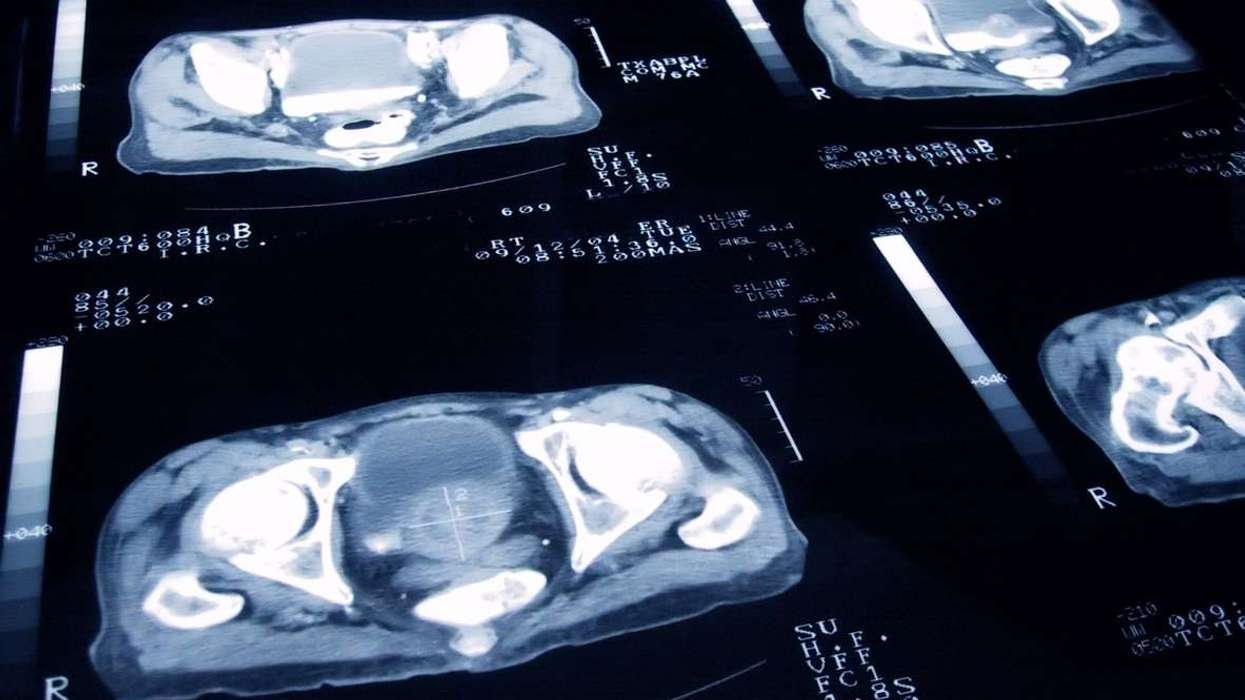

To evaluate internal organ involvement, doctors may recommend imaging and functional tests such as:

- Chest X-rays or CT scans to assess lung damage